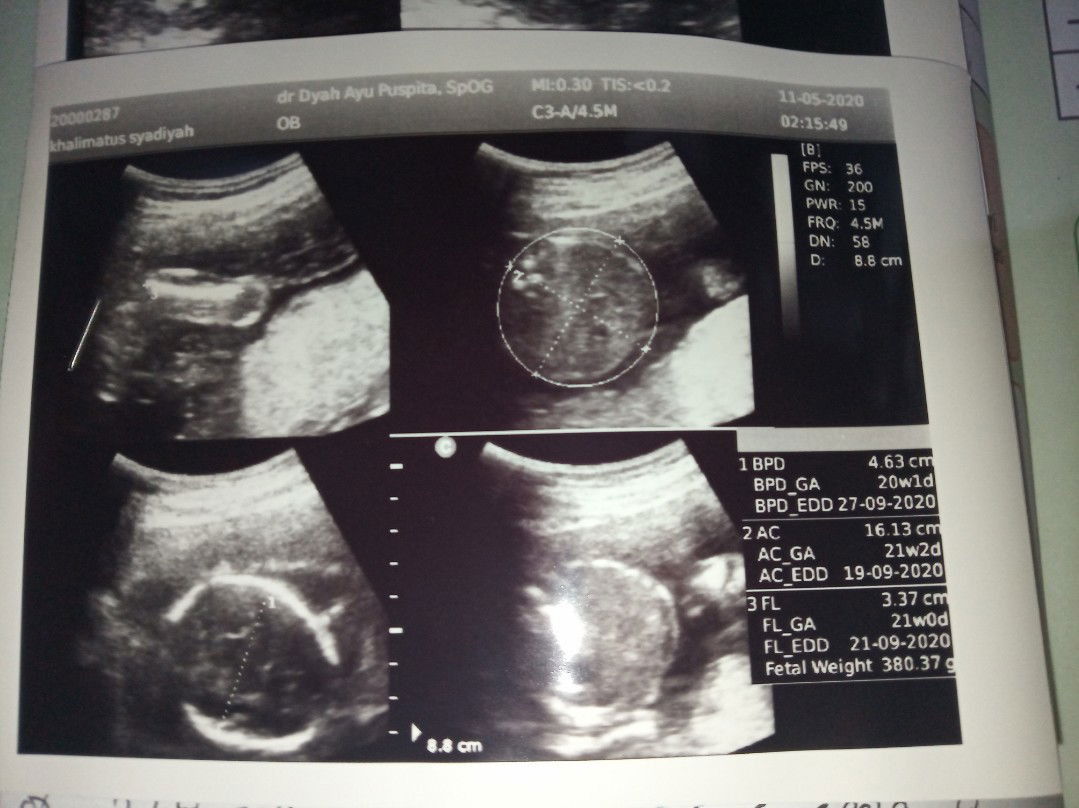

USG 21 Weeks

Alhamdulillah kata doker bayinya sehat, air ketuban cukup, detak jantung normal dan boleh lanjut ikut puasa dan seneng bgt wktu dokter nunjukin kepala, kaki, jenis kelamin dll ???